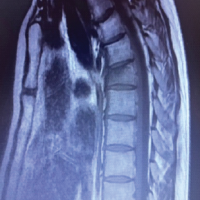

X-ray evaluation showed a pathological fracture of the T11 vertebra. Magnetic resonance imaging (MRI) dorsal spine showed expansile lytic multiloculated peripherally enhancing ill-defined lesion with a wide zone of transition replacing the entire normal marrow of the T11 vertebral body with grade II to thecal sac indentation, mild extramedullary thoracic cord compression with subtle cord edema. The lesion showed a multiloculated bubbly appearance with fluid-layered locules suggesting a possibility of ABC (Fig. 1). Differential diagnoses include Giant cell tumor, simple bone cyst, osteoblastoma, telangiectatic osteosarcoma, metastases, and plasmacytoma.

Case Report: A 68-year-old male presented to the outpatient department with complaints of left flank pain and abdominal pain for 4 months. Clinical examination showed tenderness in the thoracolumbar region with other spine examinations within normal limits. Magnetic resonance imaging dorsal spine showed an expansile lytic multiloculated lesion in the T11 vertebral body with mild extramedullary thoracic cord compression with subtle cord edema. The lesion showed a multiloculated bubbly appearance with fluid-layered locules. He underwent 2 stage procedure. In the first stage, posterior decompression, posterior stabilization, and biopsy were done. The histopathology report was consistent with ABCs. In the second stage, T11 corpectomy, tumor excision, and reconstruction with an expandable cage were done. Postoperatively his pain was reduced and was neurologically intact. At 4-year follow-up, clinically, he has excellent functional outcome and free of recurrence.